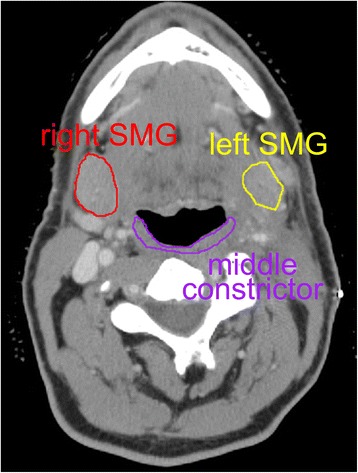

An interesting issue could be the tradeoff between cSMG sparing and pharyngeal constrictor sparing. The submandibular glands are located at a similar craniocaudal location as the middle pharyngeal constrictor muscle (Fig. 2). A potential concern is that by aggressively sparing the cSMG instead of prioritizing pharyngeal constrictor sparing, the dose to swallowing muscles could increase, worsening dysphagia. A crude comparison shows that our patients’ swallowing structure doses are similar to those in a trial of constrictor muscle sparing IMRT in which the mean constrictor dose was 58 Gy, the mean larynx dose was 48 Gy, and the mean esophageal inlet dose was 34 Gy [2]. This suggests that cSMG sparing in our series did not overly increase dose to the swallowing structures, as we routinely spared the uninvolved oral cavity and oropharynx.

Fig. 2.

Relationship of submandibular glands to middle pharyngeal constrictor muscle. There may be a tradeoff in radiation treatment planning between aggressively sparing the constrictor muscles and the contralateral submandibular gland